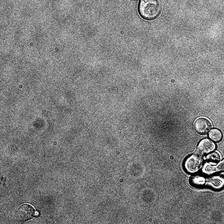

for i_img, img in enumerate(x):

rec1 = reconstructed_images1[i_img]

rec2 = reconstructed_images2[i_img]

display(ToPILImage()(img[0]))

display(ToPILImage()(rec2[0]))

display(ToPILImage()(rec1[0]))